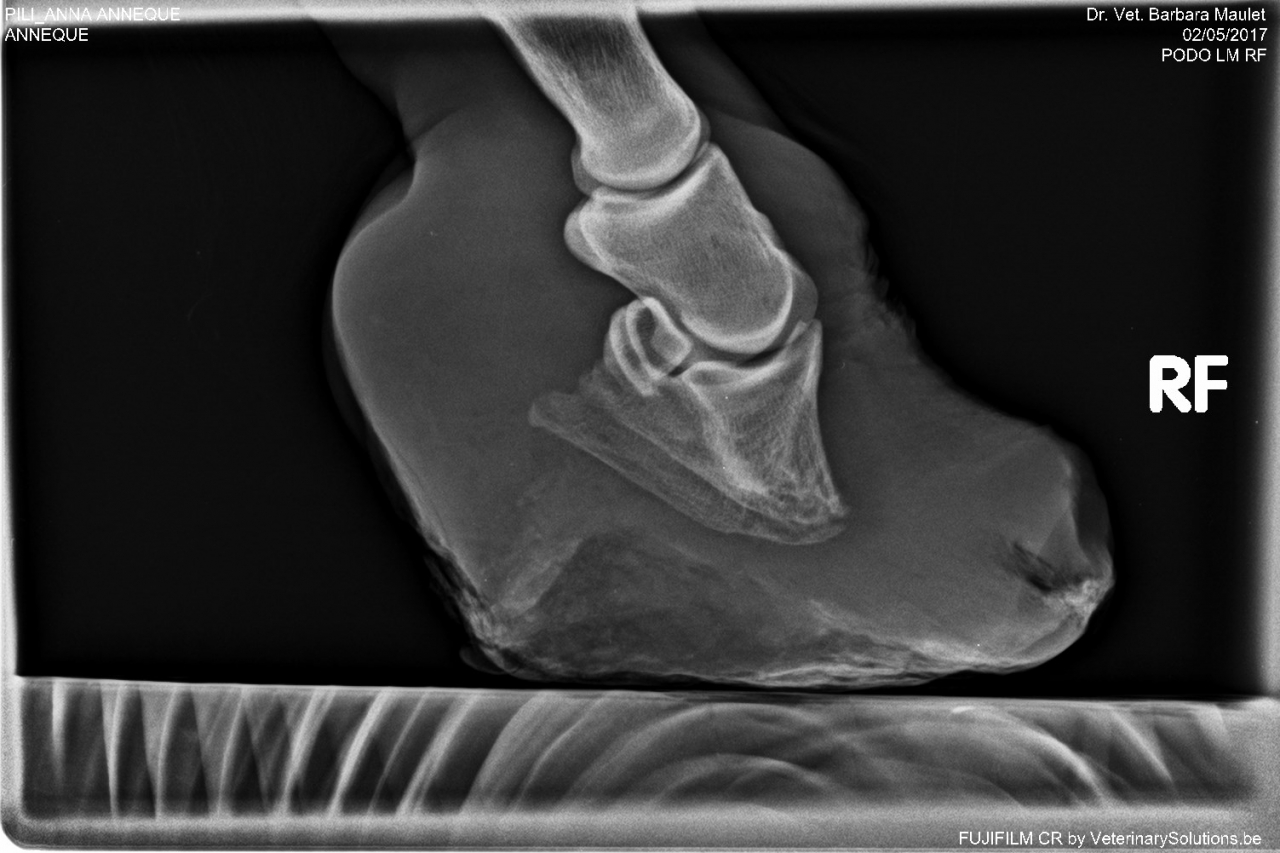

DéconnectéDire merci | j'ai fait piquer mardi la petite fourbue juste après avoir vu ses radios pour mémoire la photo: ![]() à des fins didactiques les radios ![]() ![]() non seulement il y a bascule totale de la phalange mais un gros remodelage de l'os, y avait rien à récupérer. Pipa la jument de manège a aussi été fourbue plusieurs fois, elle ne marche pas correctement des 2 antérieurs. son taux d'ACTH est à 96 ce qui ne me semble pas énorme. Les radios: ![]() ![]() basculement présent mais nettement moins important, léger remodelage. Rassurez vous le MF est passé hier ... |

| Dire merci | Les radios font froid dans le dos 😔 Bon voyage à cette petite 🌈 |

| Dire merci | les radios de la petite fourbue ![]() Elle aura au moins connu un peu de réconfort dans sa fin de vie et aura évité de longues semaines (mois, années ?) de souffrance supplémentaires |